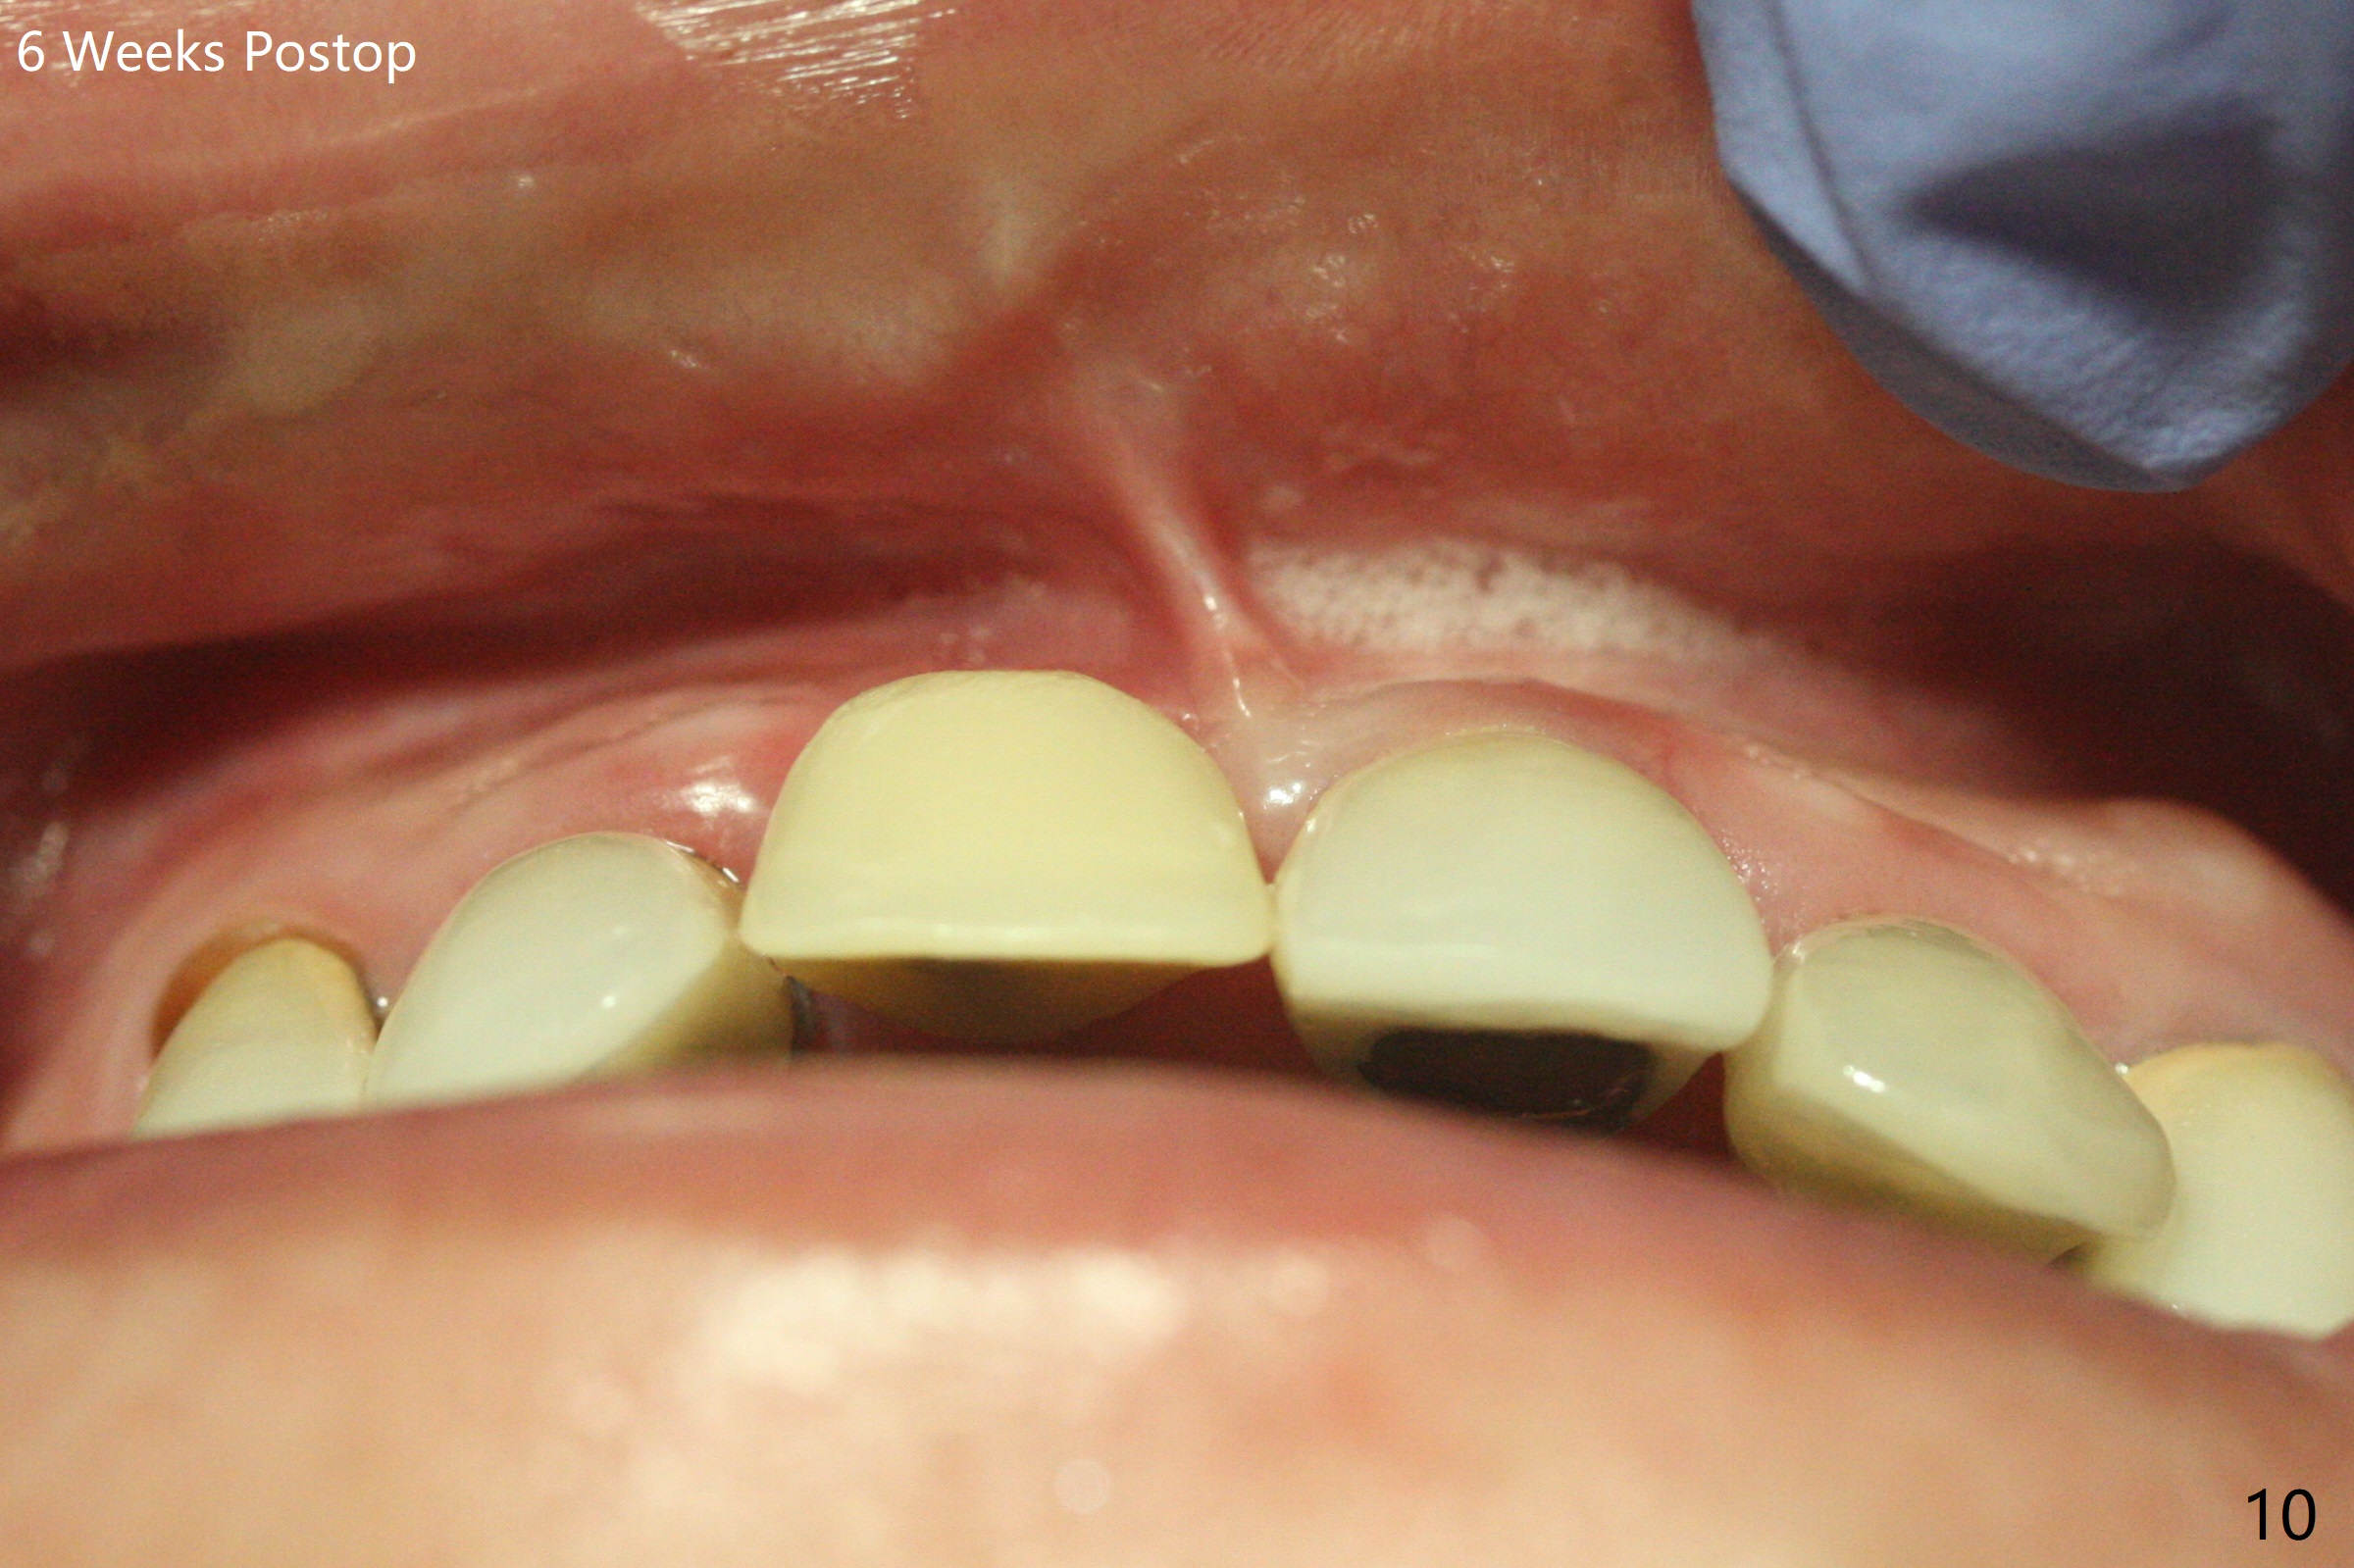

徒手初步钻洞显示方位不对(图一),重新钻洞方位尚可,好像接近鼻底(图二:红线);植入3x11.5毫米一段式植体(图三),3-5个螺纹暴露,植体似乎接近鼻底;旋转植体三趟,植体仿佛卡人鼻底,扭力大约35Ncm,植入粘性骨粉(图四,五:*)前,塞入PRF膜,紧贴颊侧粘膜,促进瘘道愈合。骨粉不仅围绕植体,而且紧贴邻牙牙根(图六(第二轮植骨:overgrafting):<)。病人术后第二周开始使用水牙线,术后三周牙龈健康多了,瘘道消失(图七)。术后六周颊侧骨壁开始塌陷(图八:>),临时牙冠颊侧颈部显得隆起(*)。调整后,牙冠外形改善(图十一至十三),取模前颊侧牙龈缘有可能下降,两个中切牙龈缘可能一致。术后3.5个月骨粉形态(图十四)与术后即刻(图六)有所不同。颊侧牙龈仍红肿轻度触痛(图十五),可能因为临时牙冠不利于局部卫生,所以决定取模制作永久性牙冠。粘固时使用临时胶水,并且涂抗菌素。另外一个可能因素是颊侧骨板薄(图十六:*),细菌感染植体螺纹,永久性牙冠粘固前,拍摄CT(放置cotton roll),必要时,植骨。永久性牙冠远中有缝隙,为了预防病人后悔,使用临时性粘固剂固定(图十七)。Return to No Caries DIO 下一个病例 一段式植体边缘制备 导板与内提升 Xin Wei, DDS, PhD, MS 1st edition 12/22/2020, last revision 06/15/2021